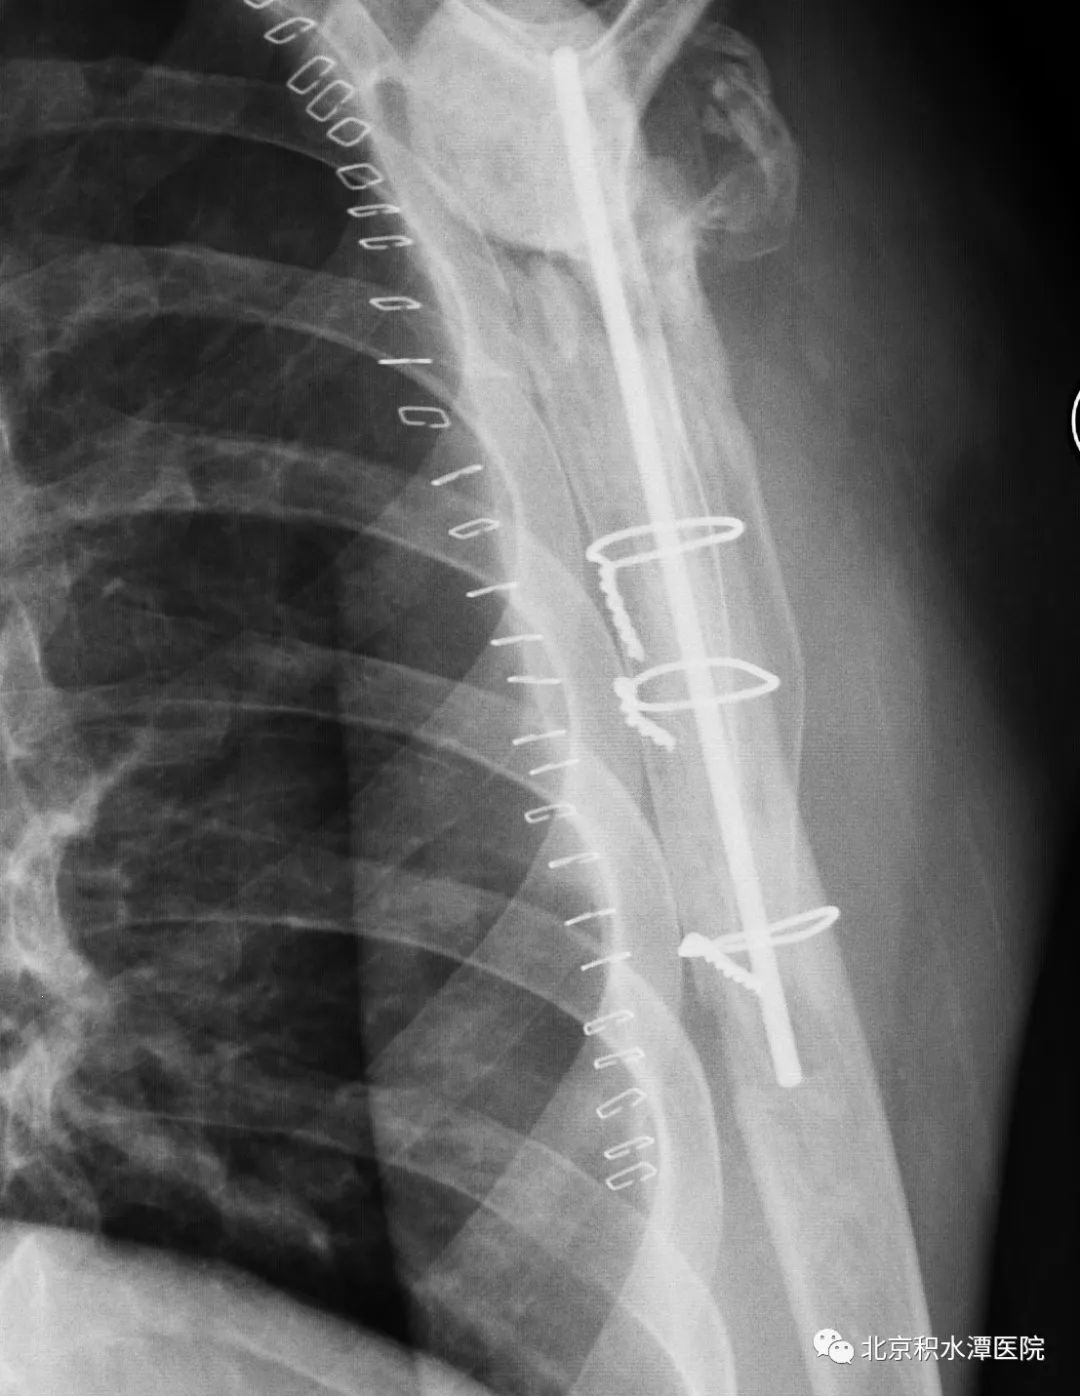

首先行假体取出、扩创控制感染,后期再行反肩关节置换。完善相关检查后,于2018年5月手术,扩创取出原假体,抗生素骨水泥植入。术中最大的难点在于肱骨侧假体、骨水泥及髓腔塞取出困难,而任何残留都可能会造成感染复发,术中采用肱骨干纵行劈开方式将假体、骨水泥和髓腔塞全部取出,并用钢丝捆扎修复,而肩胛盂侧的假体取出则较为顺利,但患者大小结节均已移位,肩袖组织完全挛缩。术后培养为表皮葡萄球菌,通过抗生素治疗,患者的感染顺利控制。

术后患者复查CT,见肩胛盂骨性重建良好。但为解决现有假体长度不足的问题,此次术后,蒋协远教授、黄强主任医师就带领团队医生与工程师团队进行了反复沟通,开始设计并定制合适的反肩假体。按健侧长度计算,肱骨近端骨缺损约8厘米,起初还在肿瘤型假体和APC方式间反复讨论,最后决定采用定制反肩假体结合异体骨(APC)的方式进行处理,同时还定制了相应长度的异体骨,以更好地恢复上肢长度和三角肌张力。

2022年8月18日,患者再次回到北京积水潭医院,蒋协远教授带领黄强主任医师和查晔军副主任医师、公茂琪主任医师等为患者进行了APC反肩置换手术治疗。术中见肩胛盂骨性结构重建良好,取出螺钉,顺利安装肩盂侧反球假体。并反复通过测量和软组织张力判断,确定了异体骨长度,安装肱骨侧假体后,以异体骨板捆扎保护,手术过程顺利,拍片见肩关节假体位置满意。